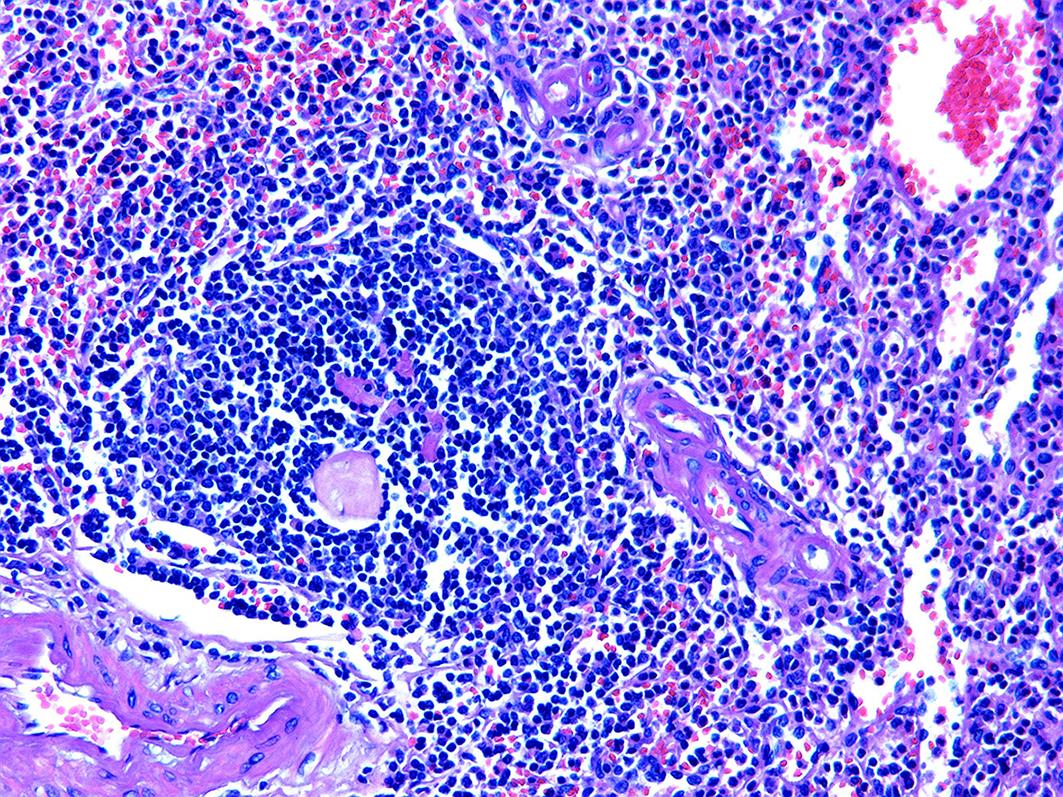

Accessory spleen refers to the spleen tissue that exists outside of the normal spleen, with a similar structure to the main spleen and certain functions. Intrapancreatic accessory spleen (IPAS) completely enveloped by the pancreas has an incidence rate of only 2%, and it is easily misdiagnosed in clinical practice due to its atypical clinical symptoms and similar radiological features to pancreatic neuroendocrine tumor, pancreatic solid pseudopapillary tumor, and other pancreatic space-occupying lesions. This article reports the clinical data of two patients with IPAS who were misdiagnosed as pancreatic neuroendocrine tumor and pancreatic solid pseudopapillary tumor, respectively, analyzes the reasons for misdiagnosis, and summarizes the experience in diagnosis and treatment, in order to improve the ability for the differential diagnosis of IPAS in clinical practice.